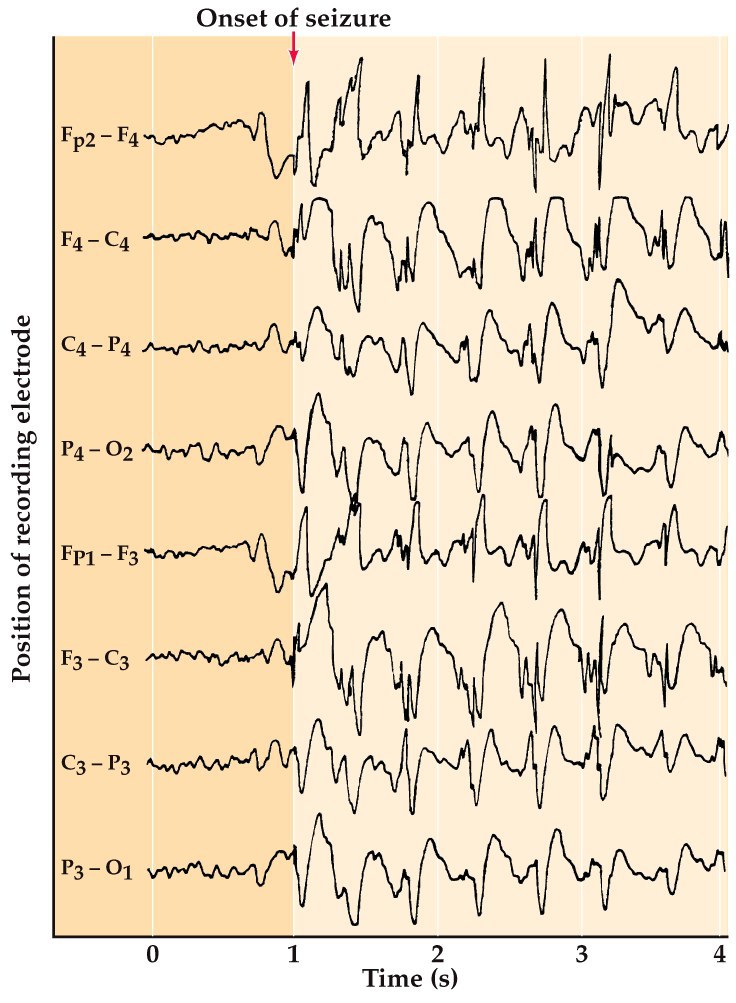

Epilepsy

Disorder characterized by periodic seizures from synchronous firing of large groups of neurons in the nervous system. Kindling and synaptic plasticity plays a role.

Reid et al., Prog Neurobiol 2009

Scheffer adn Berkovic Trends Pharm Sci 2003

McNamara et al., STKE 2006

Engel 2008, Epilepsy: A Comprehensive Textbook